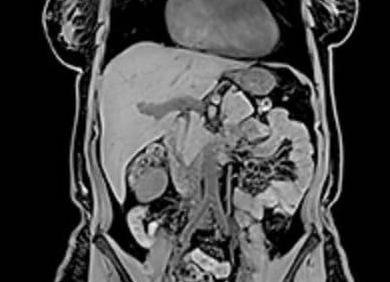

В МРТ используют магнитное поле, благодаря которому удается получить послойные снимки исследуемой области. Примечательно, что методика достаточно безопасна, особенно по сравнению с компьютерной томографией, которая основана на рентгеновском излучении. Отличительной чертой МРТ от колоноскопии является то, что для ее проведения нет необходимости проникать в полость человека и вводить в нее чужеродные предметы.

Магнитно-резонансная томография кишечника применяется для обнаружения заболеваний органа посредством передачи трехмерной картины его изображения. Примерно 3 суток до обследования нужно соблюдать диету, исключающую газообразующие и закрепляющие продукты – дрожжевую выпечку, рисовую, манную кашу, молоко, капусту, крепкий чай. Убрать вздутие поможет энтеросорбент. Для лучшего очищения кишечника можно употребить слабительное и выполнить очистительную клизму. Перед обследованием больному дают выпить специальный, визуально выделяющий кишечник при МРТ, раствор.

Магнитно-резонансная томография часто применяется для оценки состояния тонкой кишки, поскольку эта зона исследуемой области наиболее чётко визуализируема при магнитной томографии.

МРТ-диагностика других отделов кишечника обычно проводится в качестве дополнительной меры. В подобных случаях используется контрастное вещество, дающее достоверные результаты сканирования.

Магниторезонансная методика – не инвазивная процедура, которая позволяет без вреда, а также рентгеновского облучения произвести диагностику. После её проведения врач получает послойные снимки с выводом 3D картинки. В результате изучения этих материалов назначается лечение.